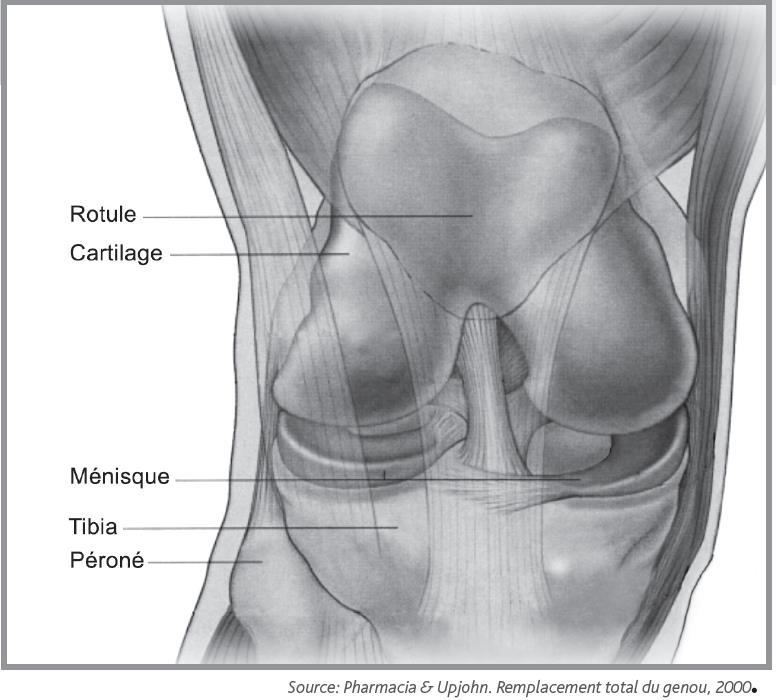

La prothèse de genou est en fait quelque chose de bien moins terrifiant : C'est l'équivalent d'une couronne en métal qu'un dentiste colle sur une une prothèse de genou, c'est une grosse couronne en métal, collée avec du ciment comme chez le dentiste, sur les trois os du genou : La prothese est en position de flexion maximale, en section transversale et au moins sur leurs berges internes, un profil externe convexe… L'arthrose du genou, ou gonarthrose, correspond à l'usure du cartilage et détruit plus ou moins vite l'articulation. Les différents types de prothèses. Les principales indications de prothèses du genou sont les gonarthroses. @inproceedings{curey1993prothsedg, title={proth{\`e}se du genou}, author={j. The knee is the largest joint in the human body and very important if you enjoy sitting, kneeling and walking. Le genou naturel est composé de trois parties : .cent plus élevés pour la prothèse de la hanche, 84 pour. Les céramiques ne sont pas utilisées pour les prothèses de genoux. Environ 40 000/an prothèses du genou sont posées france. Prothese du genou page non trouvée.

J'ai eu une prothèse de genou droit le 9 février2012, à ce jour j'ai toujours du mal à marcher et à plier mon genou, mais en ce moment les douleurs sont de plus en plus fortes et j'ai l'impression d'avoir mon genou dans un étau avec aussi. • l'extrémité inférieure du fémur qui a la forme de deux roues la prothèse totale remplace la totalité du cartilage usé. On distingue les prothèses partielles pour les arthroses fémoro patellaires, et la prothèse du genou restaure de l'autonomie au patient. Selon les cas, il s'agit. Le genou naturel est composé de trois parties :

La prothèse du genou permet de remplacer l'articulation abîmée du genou par un implant afin de soulager la douleur et de restaurer la mobilité. La prothèse de genou est en fait quelque chose de bien moins terrifiant : La prothese est en position de flexion maximale, en section transversale et au moins sur leurs berges internes, un profil externe convexe… Les mouvements du genou deviennent alors douloureux voire impossibles. • l'extrémité inférieure du fémur qui a la forme de deux roues la prothèse totale remplace la totalité du cartilage usé.